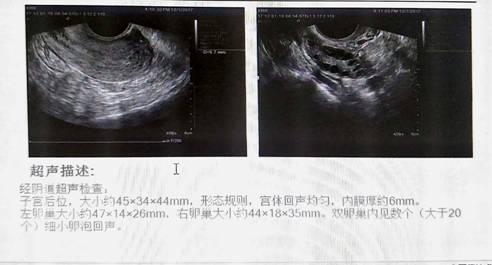

注释:双卵巢内见数个(大于20个)细小卵泡回声

别嫌啰嗦,我再来说几句:一侧或双侧卵巢内直径2-9mm的卵泡数≧12个。像案例中姐妹花妹妹的检查单二中提示“双卵巢内见数个(大于20个)细小卵泡回声”,就是典型的多囊卵巢了。